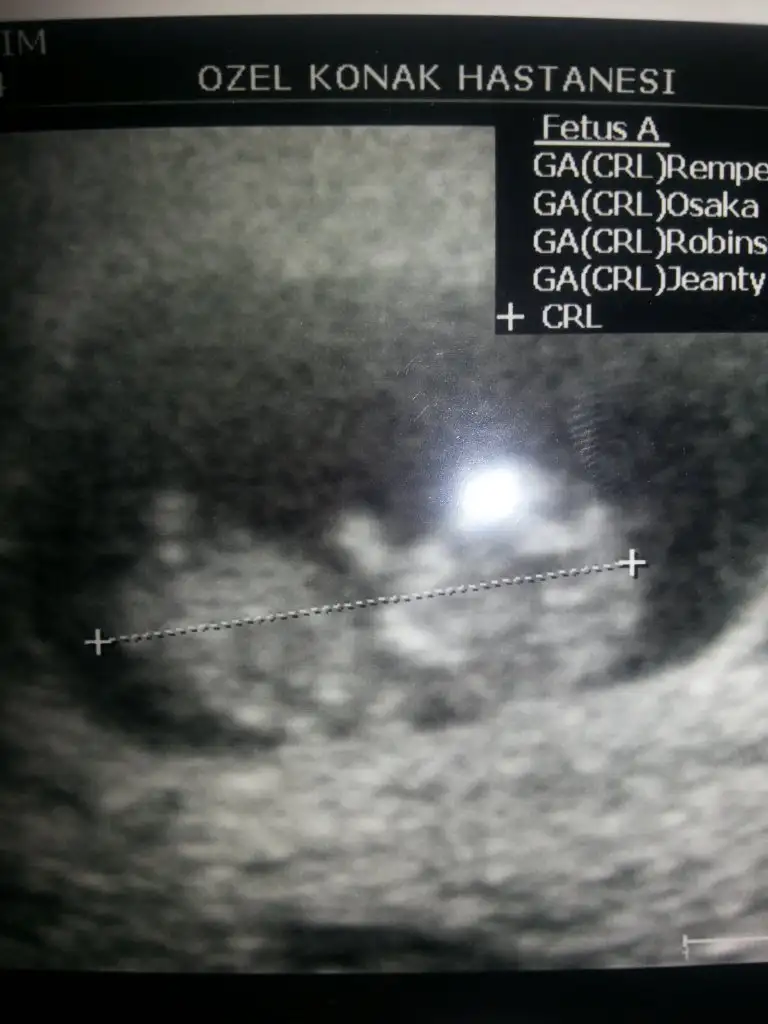

dr soylemeden siz gorun genital nub teorisi ( bebegin cinsiyeti)

Evveet teyzoşlarıı yorumları alalım bu arada ikiz olduğu için orda iki bebek var ama bende hangisi 1 hangisi 2 bilmiyorum

Bi dk ultrason görüntüsünden bişey fark ettim aynı hastaneye gidiyoruzzz :) :)) Ben Gülçin Aydara gidiyorum Erkan beyy çok yoğun diyee :)

Çok baktı geçen hafta ama malesef bişey söylemek için çok erken dedi 12 haziranda tekrar gel o zaman belli olur dedi... Bende sabırsızlıkla bekliyorum ciciler almak için :)